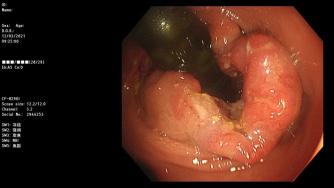

镜下可见

检查所见:进镜可见肛缘上方环周火山样占位病变,质脆易出血。检查结论:直肠癌